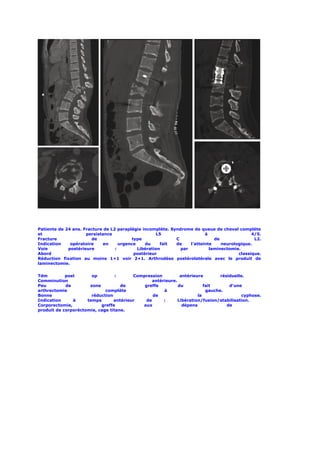

Patiente de 24 ans. Fracture de L2 paraplégie incomplète. Syndrome de queue de cheval complète

et                   persistance                     L5                  à                   4/5.

Fracture                de               type               C                de               L2.

Indication    opératoire     en     urgence    du     fait  de    l’atteinte    neurologique.

Voie         postérieure          :         Libération        par          laminectomie.

Abord                                     postérieur                                   classique.

Réduction fixation au moins 1+1 voir 2+1. Arthrodèse postérolatérale avec le produit de

laminectomie.

Tdm         post       op         :      Compression          antérieure        résiduelle.

Comminution                                      antérieure.

Peu         de        zone          de       greffe          du          fait       d’une

arthrectomie                 complète                 à                   gauche.

Bonne                  réduction                 de                   la                 cyphose.

Indication     à     temps       antérieur    de      :      Libération/fusion/stabilisation.

Corporectomie,             greffe           aux                dépens              de

produit de corporéctomie, cage titane.